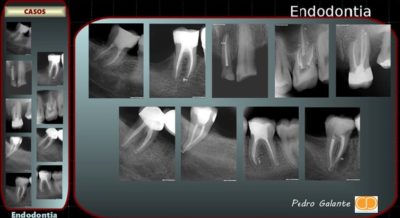

“Endodontia é a ciência médica, na esfera da dentária, que lida com os tecidos internos do dente, da sua patologia e do seu tratamento. Quando estes tecidos ou os que rodeiam o dente ficam doentes ou são danificados por cárie ou trauma, o tratamento endodôntico é o que permite salvar o dente na cavidade oral” (AAE – American Association of Endodontics).

Um endodontista é uma pessoa que executa desvitalizações, ou seja, ele prepara os canais do dente, desinfeta-os das bactérias e obtura-os com material biocompatível. Na prática, os dentes que precisam deste tipo de terapia, são por exemplo aqueles dentes que o mantiveram acordado a noite toda. Apresentam uma patologia chamada de “pulpite” – inflamação do tecido pulpar, ou apresentam um abcesso ou fístulas. Também podem ser dentes que radiograficamente apresentam um quisto ou um granuloma.

Nos últimos anos tem havido uma revolução completa no campo da Endodontia, onde os dentes que no passado costumavam ser extraídos, hoje podem ser facilmente tratados com terapia conservadora. Entre as várias inovações, o microscópio operatório merece uma posição privilegiada neste tratamento.